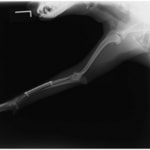

症例3:キルシュナーワイヤーのピンニングによる整復

ペルシャ猫 11ヶ月齢 雄

他院にて左大腿骨遠位の成長板骨折(salter-harrisⅠ型)が認められており、治療相談を目的として来院。当院にて、キルシュナーワイヤーを用いたピンニングにより骨折部位の整復を行いました。術後の経過は良好で、現在も経過観察中です。

術前レントゲン

術後レントゲン